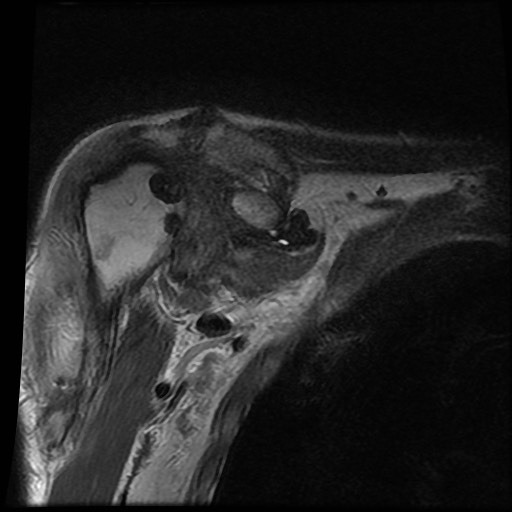

Tiếp tục xem hình ảnh MRI của bệnh nhân này.

Hình ảnh MRI:

Tràn dịch lan tỏa tất cả các khớp cổ tay.

Phù tủy xương lan tỏa tất cả các xương cổ tay.

Bào mòn xương, ví dụ tại xương thuyền, xương đầu và xương móc.

Phá hủy khe khớp và sụn khớp, rõ nhất tại khớp STT và CMC4/5.